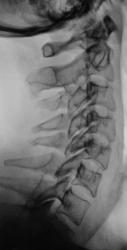

На рентгенограммах стато-функциональные изменения в шейном отделе выражены не отчетливо, можно описать как патологию, но можно описать и как норму, а вот увеличение ширины ключично-акромиального сочленения есть, возможно имеет место быть старый разрыв связок ключично-акромиального сочленения.